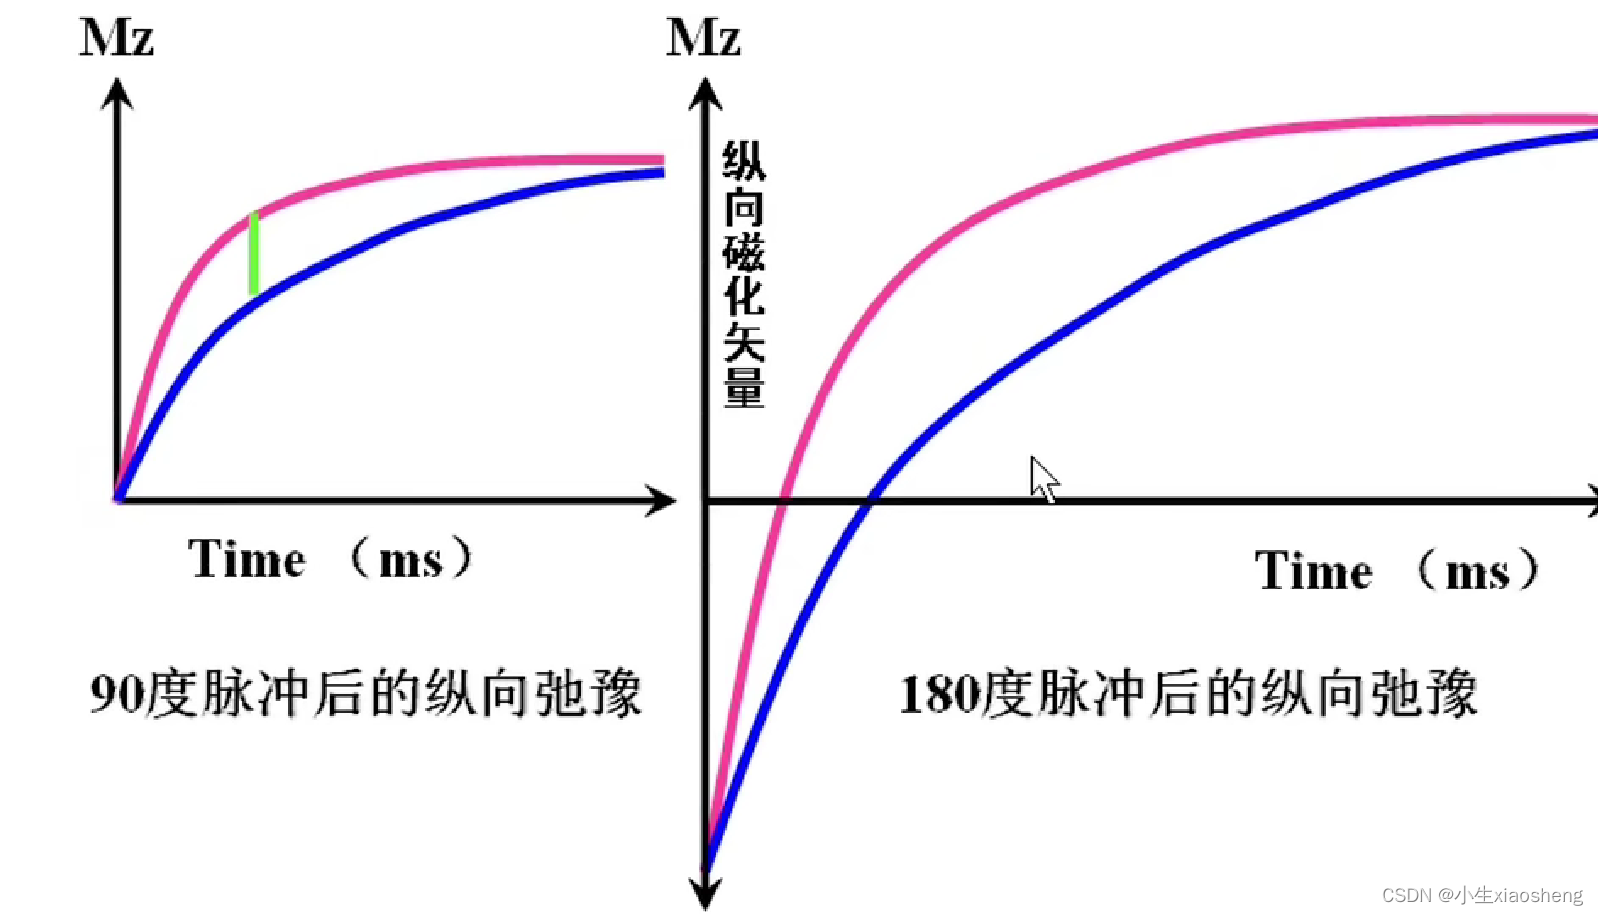

T1(纵向弛豫时间):当射频脉冲信号解除后,激发状态的氢原子核会慢慢释放能量,同时相位和能级会恢复到开始状态、磁化矢量也会恢复到平衡状态。这个过程被称为纵向弛豫

说明时间越长对应的差距也就越大,说明其结果对比好,更容易看出图片。其中TI为反转时间